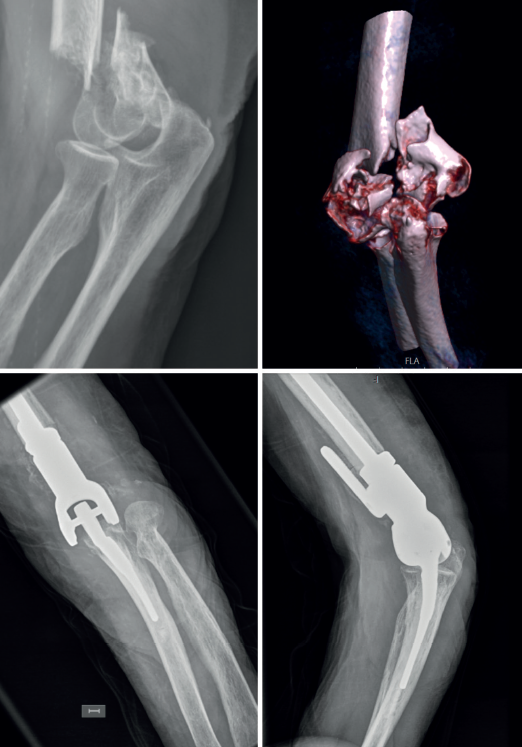

En consonancia con lo anterior, nosotros creemos que en la selección de la fractura que se va a intervenir con PTCodo es importante el uso de la tomografía computarizada para valorar y clasificar el tipo de fractura que tratar, porque si nos quedásemos con un estudio de radiología convencional difícilmente podríamos clasificar la fractura en el sistema AO (Figura 3). Todos los estudios incluidos para el tratamiento de fracturas de húmero distal mayoritariamente son fracturas de tipo C, pero en algunos casos A y B, por lo que nosotros adoptamos un protocolo propuesto por la Clínica Mayo para dicho tratamiento (Figura 2)(67), siendo muchas veces la decisión de emplear una PTCodo como tratamiento intraoperatoria. Mayoritariamente son fracturas cerradas, pero la existencia de fracturas abiertas no es una contraindicación, incluso se comunican fracturas de tipo IIIB de Gustilo(68).